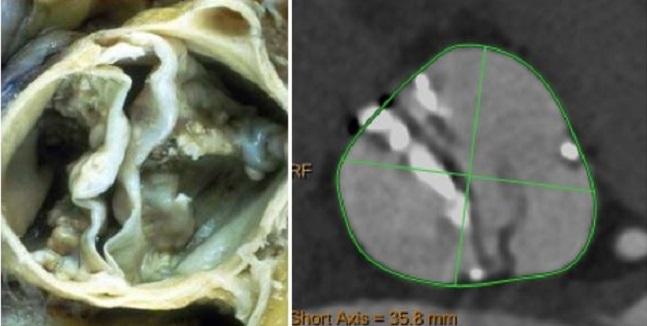

Bicuspid aortic valve (bav) is the most common congenital cardiac pathology which results from the fusion of two adjacent aortic valve cusps. Freedom from reoperation at 20 years was approximately 96% for the overall cohort with one bicuspid patient undergoing reoperation at eight years from index valve repair. The survival of patients with bav following aortic valve surgery was excellent and similar to that of the general population.

Kari et al.from stanford university analyzed 75 bav patients undergoing reimplantation technique for either ar (31%) or root aneurysm (69%) (25). A classification system for the bicuspid aortic valve from 304 surgical specimens. In 1 large surgical series, 13% of surgically excised valves at the time of aortic valve replacement were for pure aortic incompetence.